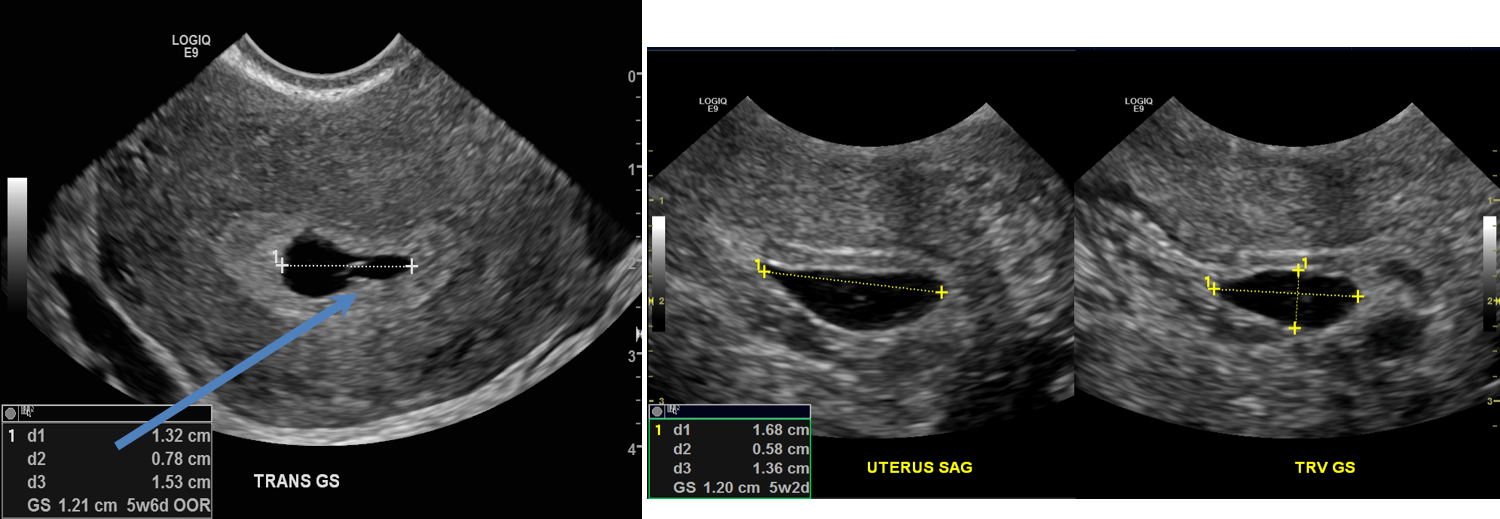

- Initial images show a gestational sac and a yolk sac (blue arrow). Follow-up ultrasound (image on the right) showed a gestational sac that was similar in size. No heartbeat was identified.